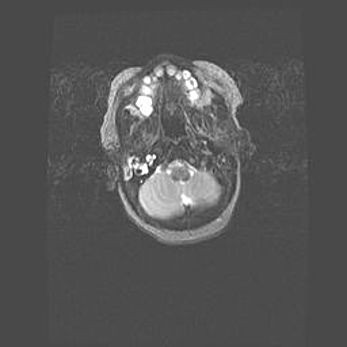

Мальформация Денди-Уокера. Киста задней черепной ямки.

Агенезия мозолистого тела.

Возраст: 2,5 месяца

Вес: 2420 г

Пол: женский

Окружность головы: 37 см

Срок гестации: 32 недели

Мальформация Денди—Уокера — редкий вид патологии ЦНС, представляющий собой врожденный порок развития каудального отдела ствола и червя мозжечка, ведущий к неполному раскрытию срединной (Мажанди) и латеральных (Лушка) апертур IV желудочка мозга. Для этогно синдрома характерна триада симптомов: гипотрофия червя мозжечка и/или полушарий мозжечка, кисты задней черепной ямки, гидроцефалия различной степени. В 70% случаев порок сочетается и с другими аномалиями головного мозга, в частности с агенезией мозолистого тела.